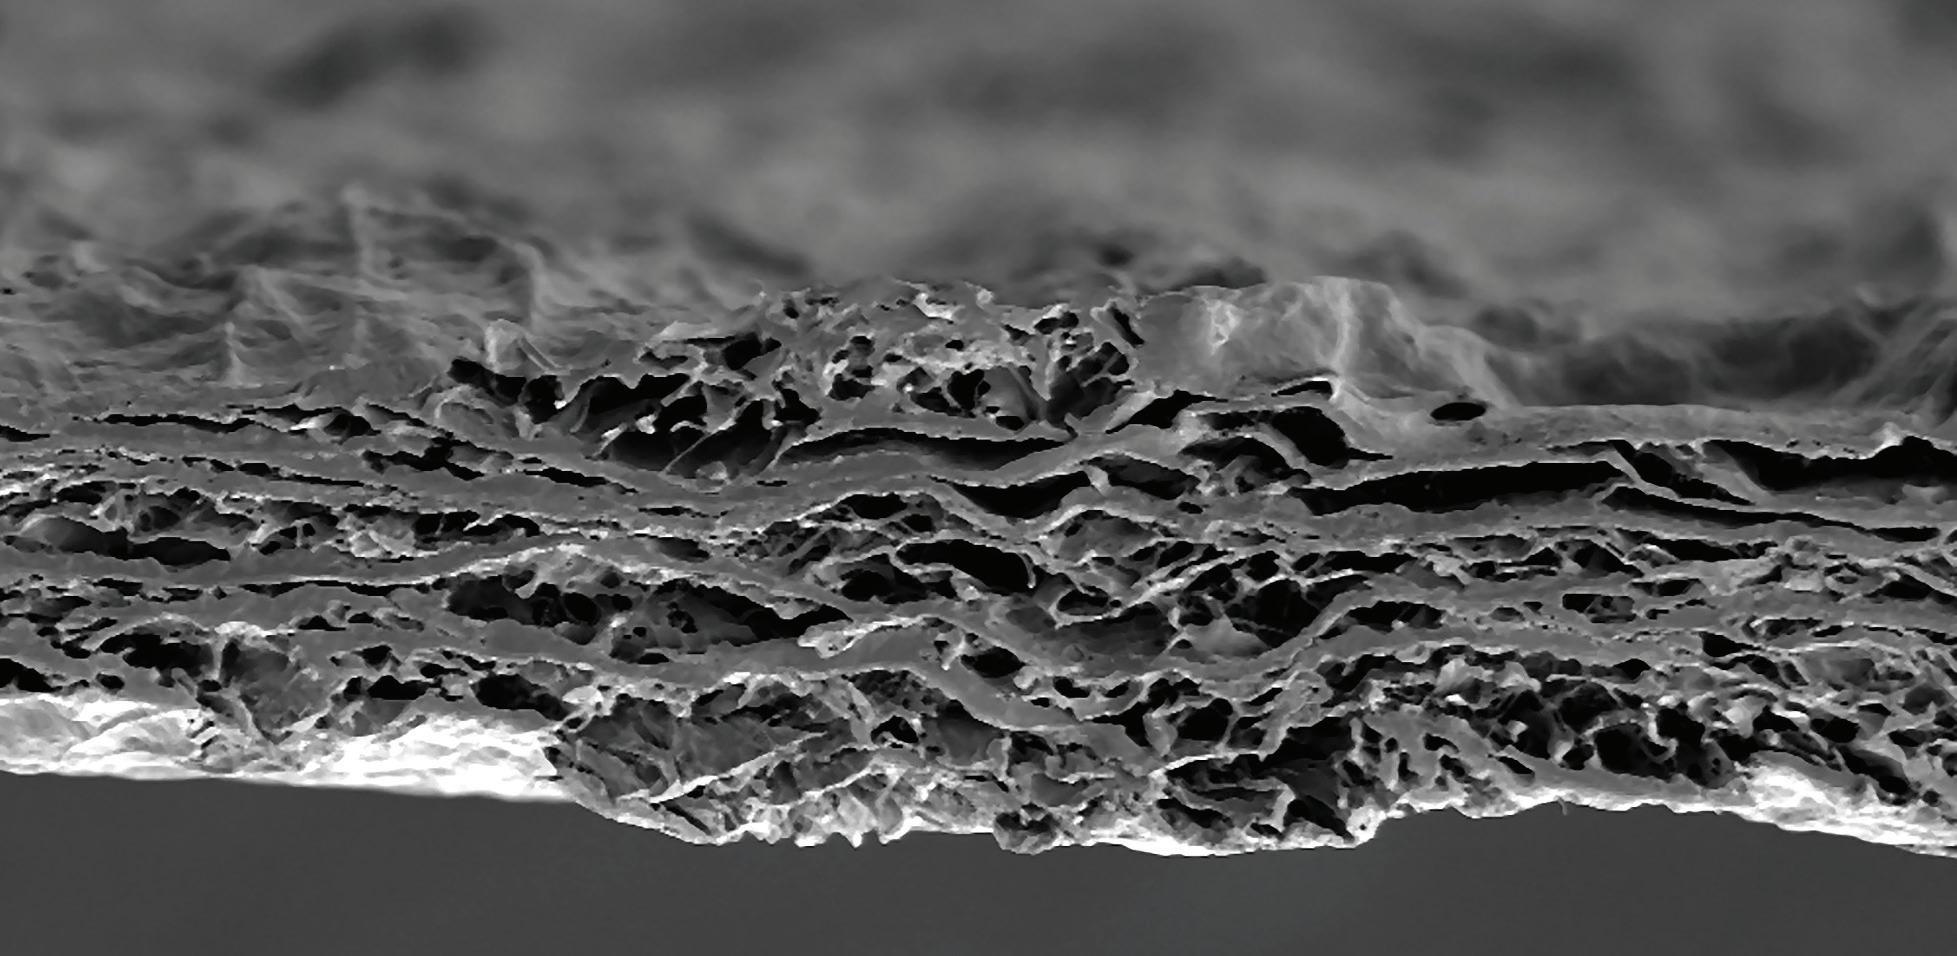

Leziunile carioase din regiunea radiculară reprezintă o provocare majoră în practica de rutină. Pe lângă faptul că sunt greu de detectat (diagnosticul este adesea o constatare radiologică), acestea sunt și foarte dificile din cauza proximității lor față de țesutul pulpar și a accesului anevoios pentru procedurile de restaurare.

Biodentine™ este un material pe bază de silicat de calciu care prezintă, printre principalele sale proprietăți, bioactivitate, rezistență la compresiune și timp scurt de priză. Aceste calități fac posibilă utilizarea Biodentine™ ca material de obturare într-o singură etapă în cazul trata-

mentelor conservatoare ale pulpei, cu sau fără expunere.1,2,3

Spre deosebire de MTA, ale cărui indicații sunt mai concentrate pe endodonție, Biodentine™ a dovedit rezultate în regenerarea pulpei.4 Comparativ cu ionomerii de sticlă, Biodentine™ este mai rezistent, fiind și bioactiv.3 Această ultimă caracteristică nu se regăsește în CIS-uri, care nu sunt indicate pentru aplicarea direct pe pulpă fără un alt material ca liner sau bază, cum ar fi hidroxidul de calciu sau MTA.5,6,7,8,9 Mai mult, Biodentine™ nu colorează structura dentară așa cum o face MTA.10 Prin urmare, este o opțiune excelentă pentru cazurile de procese carioase profunde, chiar și în cele

cu implicarea directă a pulpei. Acest articol prezintă o serie dintre caracteristicile și indicațiile Biodentine™ ilustrate printr-o prezentare de caz.